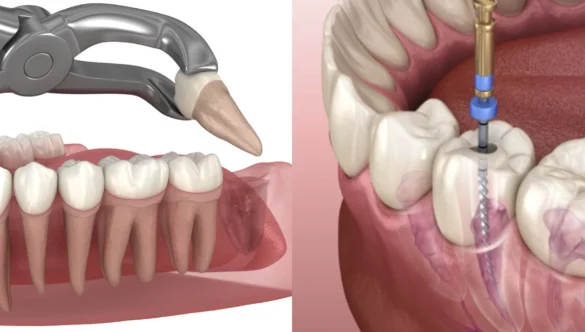

DR. HAPPY PATEL is a dental surgeon with 10 years of expertise. She is the owner and director of NOVA Dental Hospital. Her area of expertise is all dental treatments like dental implants, cosmetic dental treatments and smile makeovers, painless root canal treatments, full mouth rehabilitation treatments, fixed and removable dentures, and child dental care.

DR. HAPPY PATEL is dedicated to the most advanced dental treatment and technology. Incorporating proven systems that make your appointments better, faster, and safer. This view of technology makes our dental procedures more conservative and less expensive for our dental patients. she is very particular about sterilization and hygiene protocols.